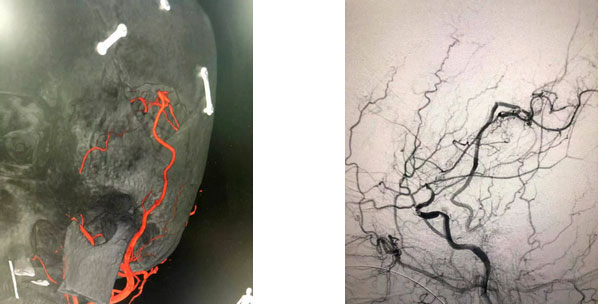

▲ 术后影像

▲ 吻合口完美缝合

术后,经过评估,患者脑血流得到明显改善,患者目前恢复良好,已经由术前浅昏迷状态慢慢清醒,并可以下床活动。